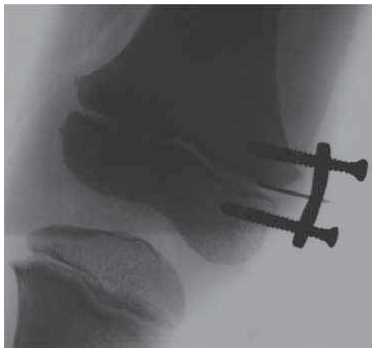

Surgical intervention was performed under general anesthesia. A linear 15-cm-long incision of the skin and subcutaneous tissue was made along the outer surface of the right thigh in the upper and middle third. A fibrous cord with a width of up to 1.5 cm, fused to the iliotibial tract and surrounding soft tissues with multiple scarring cords was isolated. The cord was isolated from the surrounding soft tissues. Right thigh adduction caused it to stretched, limiting the amplitude of movements in the right hip joint. Up to 15 cm of the cord was excised (Fig. 5). The wound was drained and sutured layer-by-layer. In addition, a tenotomy of subspinal muscles was performed through a 4-cm-long access channel along the anteroexternal surface of the proximal part of the right thigh, and the fibrous cords that limited abduction in the right hip joint were transected. The wound was drained and sutured layer-by-layer. The level of the distal growth zone of the right femur was determined under the control of the electronic optical transducer. Using a 2-cm-long access channel, the distal metaepiphyseal growth zone of the right femur was isolated and blocked using an 8-shaped plate with two screws inserted into the metaphyseal and epiphyseal sections of the bone (Fig. 6). The wound was sutured layer-by-layer. The right lower limb was fixed using an antirotation plaster cast. The postoperative period proceeded without complications. The wounds healed with primary tension and the pediatric patient was discharged from the hospital in a satisfactory condition.

Fig. 5. Fibrous cord (indicated using the gauze holder) (a); excised part of fibrous cord (b); and postoperative fixation of the right lower limb (c)

Fig. 6. X-ray of the right knee joint at the stage of blocking the medial portion of the distal femoral growth zone with an eight-shaped plate